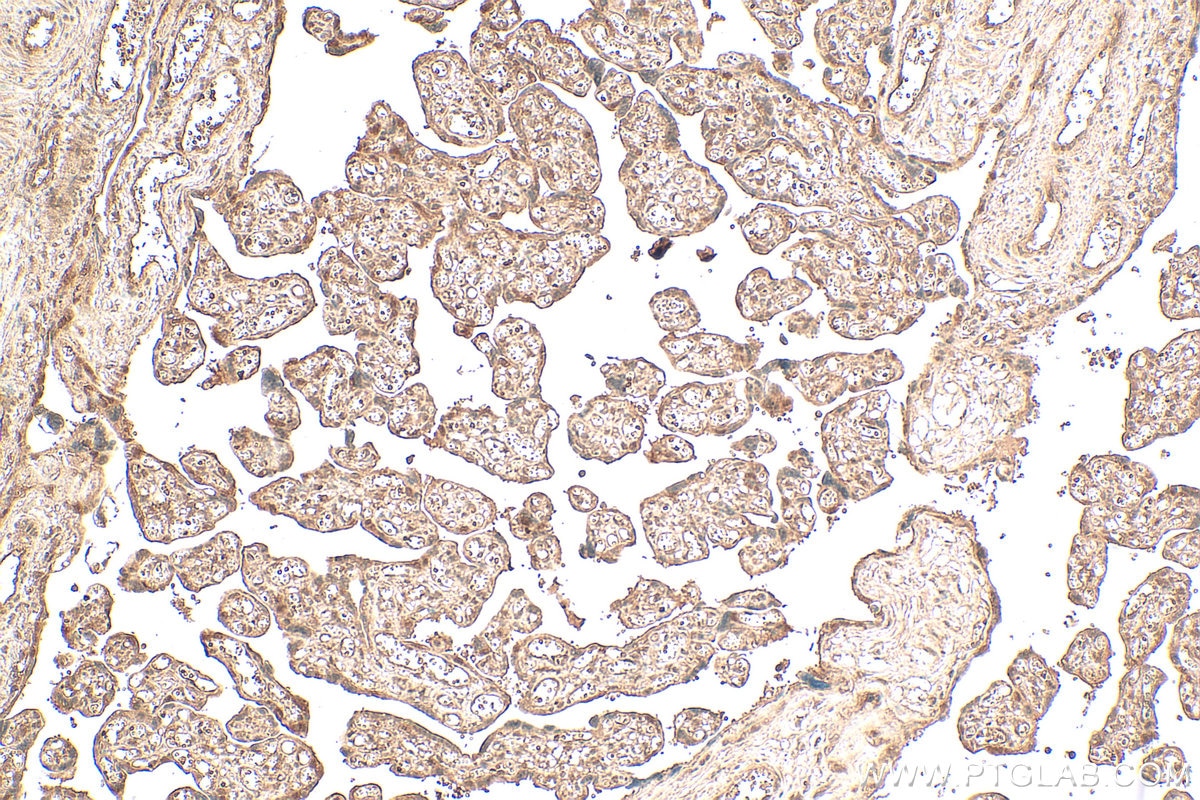

| Positive IHC detected in | human placenta tissue Note: suggested antigen retrieval with TE buffer pH 9.0; (*) Alternatively, antigen retrieval may be performed with citrate buffer pH 6.0 |

| Immunohistochemistry (IHC) | IHC : 1:50-1:500 |